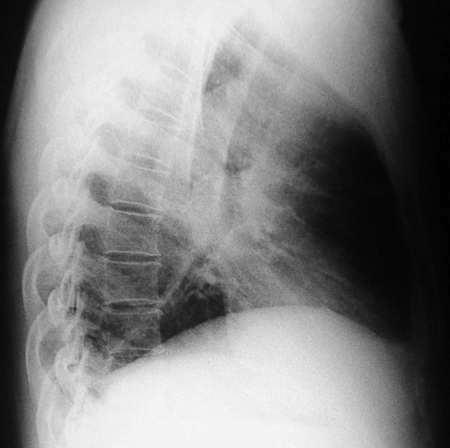

男,42岁。半年前体检发现右侧肺门肿大,mri示右侧肺门淋巴结肿大。腰背部疼痛伴右腿麻木1月入院。腹部b超示肝、胆、胰腺、脾、肾、前列腺及膀胱未见异常。afp、cea、ca199均正常。

胸部mri是半年前的,而胸部 增强ct是目前的,二者变化不大,肺部好像也没啥。

增强图像显示不清,好像有肺门及纵隔与腋下淋巴结肿大,右侧胸腔积液,腰1椎体骨质破坏,椎旁软组织肿块形成,其后硬脊膜囊明显受压。考虑淋巴瘤可能。其他待排。

腰椎骨质破坏,但未侵及椎间盘,椎前软组织肿胀,考虑腰椎转移瘤可能